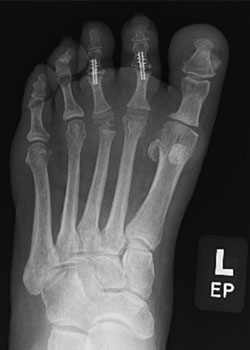

Lapiplasty Bunion Surgery with Dr. Teichman - BeforeBefore

Lapiplasty Bunion Surgery with Dr. Teichman - AfterAfter